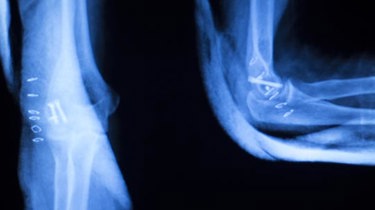

Røntgenbilleder kan i princippet anvendes til gengivelse af alle dele / vævstyper i kroppen, men det anvendes hovedsageligt til at undersøge knoglerne og brystkassen.

Ved en røntgenundersøgelse anvendes der røntgenstråler, som er usynlige, elektromagnetiske stråler med kort bølgelængde. Når et røntgenbillede optages, sendes røntgenstrålerne gennem patienten og rammer en fotografisk film, som bliver farvet mere eller mindre sort afhængig af, hvor meget af strålingen, der bliver optaget fra personens kropsvæv undervejs. Det betyder, at det hårde væv (knoglevæv) optager meget stråling og dermed bliver til hvide skygger på røntgenbilledet.